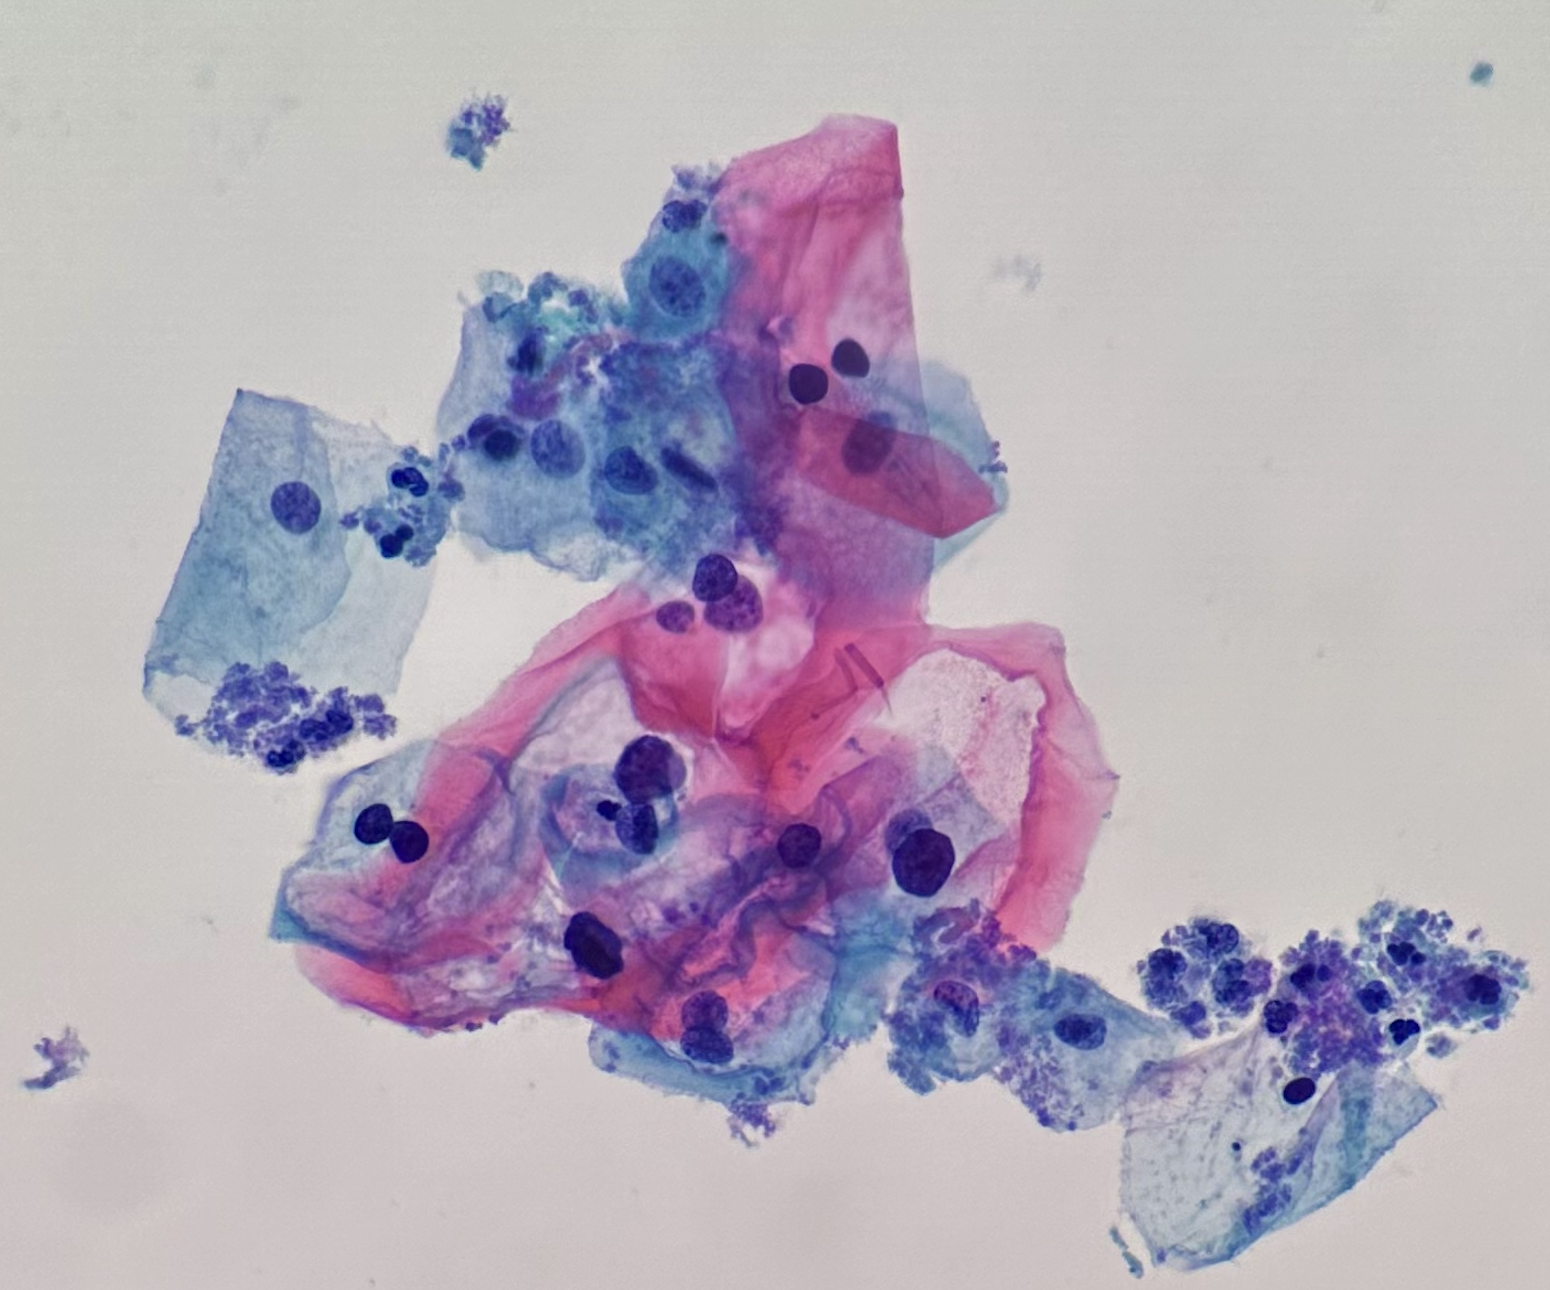

Our favorite Directory image of the week is from Mariana Cezar de Andrade Ribeiro, M.D.

Subspecialty: Cytopathology

Diagnosis: Papillary thyroid carcinoma - classic